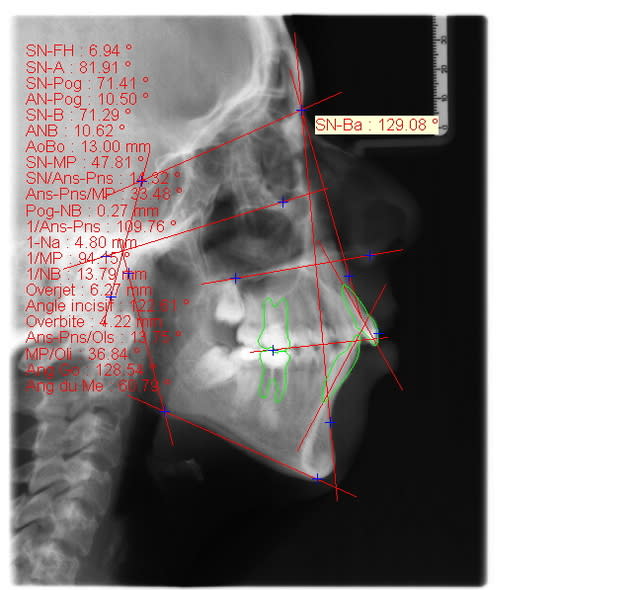

Pourtant, dancha, sans faire la tele, on a bien un SNA tres aggrandi, non?

> Pourtant, dancha, sans faire la télé, on a bien un SNA très agrandi, non?

Si, tu as raison sur ce point.

S'agit il d'une patiente de typologie chinoise ou de race jaune? Dans ce cas la typologie ethenique donne des valeurs differentes du type caucasien et les analyses cephalometriques doivent etre prises avec prudence. L'etude morphologique doit primer dans ce cas la.

Saïd a très opportunément et justement évoqué le problème ethnique.

Cette patiente est d’origine marocaine. Il faut savoir que dans certaines régions du Maroc certains autochtones sont hyperdivergentes++ dans un profil relativement convexe.

Si sa famille est elle-même de cette typologie, doit-on vraiment mettre cette jeune personne dans le moule caucasien ?

Quelle est alors la valeur diagnostique de la mesure d’un angle comme SNA, est-ce suffisant pour justifier une chirurgie ?